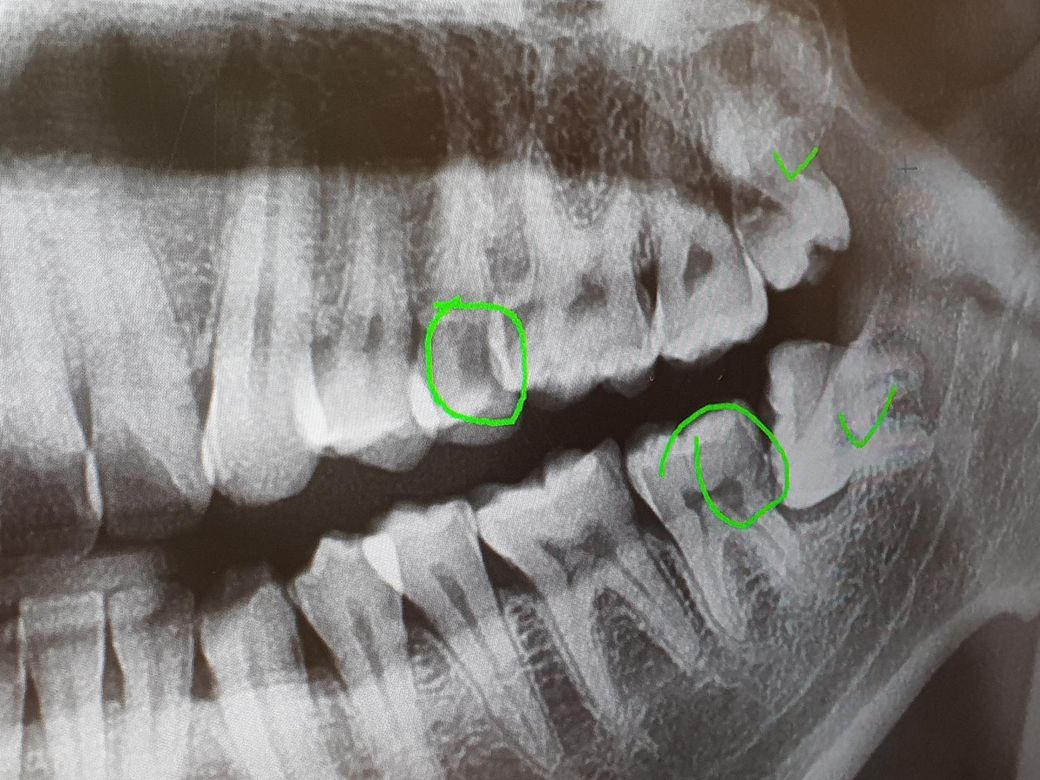

정기검짐으로 충치검사를 했습니다. 위쪽 표시된 부분에 충치가 있는건가요. 치과의사마다 의견이 다릅니다. 아프거나 시리지는 않습니다

사진만으로 100% 진단을 내리기는 원래 어렵습니다.

육안으로 보는 것과 함께 합쳐져야 정확한 진단이 완성되지요.

그럼에도 불구하고 아래 위 치아 2개다 충치가 있을 가능성이 매우 높아 보입니다.

위 치아는 육안으로 충치가 있는지 보일테고, 아래 경우에도 사랑니를 발치하고 육안으로 확인 후 치료를 진행해야 될 것 같습니다.

사진상으로는 표시한 부분이 충치가 맞는거 같습니다. 더 정확한건 작은 엑스레이사진을 찍어보고 아래쪽은 사랑니 발치를 하고나서 다시 확인 해보시는게 좋을것같습니다.

파노라마 엑스레이 사진은 겹쳐서 인접면 충치를 정확히 진단하기는 어렵고요 치근단 사진을 찍어보면 좋을 것 같습니다 충치가 의심되는 상황은 맞습니다